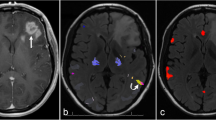

a For the same data, different activation thresholds (top), combined with different spatial masks (middle), can result in different laterality index (LI) results (bottom). For the spatial masks, green and blue represent masks for Broca’s and Wernicke’s areas, respectively. In the line plot, at low thresholds, LIs for the green and blue masks are similar, but at high thresholds, LIs for green become negative, while those for blue become more positive. b Functionally and anatomically defined language masks projected onto a pial surface. The functional mask is derived from the Neurosynth functional neuroimaging meta-analysis platform, thresholded and p-corrected ≤ 0.01; the anatomical mask is derived from the Harvard–Oxford cortical atlas. c Group-level activation maps for each of the 4 fMRI tasks (1 control task and 3 language tasks) show voxels that have higher activation levels during the active blocks compared to the control blocks using a GLM and p-corrected ≤ 0.01 after TFCE. AL anterior-left brain orientation, AT auditory tones, PL passive listening, MR mental rhyming, VG verb generation

In general, LI results depend crucially on both thresholds and masks, as illustrated in Fig. 1a [19]. Specifically, to compute LIs, activation maps are first “thresholded” at a particular statistical level and then “masked” to only count voxels within a specified region of interest. In Fig. 1a, green and blue represent masks for Broca’s and Wernicke’s areas, respectively. In the plot of resulting LIs, we see that for the same underlying activation, low statistical thresholds produced LIs that were similar for Broca’s and Wernicke’s masks, but higher thresholds produced divergent results, with LIs for Broca’s reversing from positive to negative.

We compared anatomically and functionally derived language masks for determining language laterality. The anatomical mask consisted of bilateral cortical regions corresponding to Broca’s and Wernicke’s language areas derived from the Harvard–Oxford atlas [20]. Specifically, Broca’s area was defined as the inferior frontal gyrus, pars triangularis, and pars opercularis, and Wernicke’s area as the planum temporale and adjacent superior temporal gyrus [3]. The functional mask was generated using the Neurosynth meta-analytic package from an analysis of approximately 1100 published fMRI studies and 43,000 activations based on the term “language” with no additional thresholding applied [21]. The functional mask was created by reflecting the left-hemisphere meta-activation map across midline and excluding non-cortical brain regions (Fig. 1c). For each mask, we defined anterior and posterior submasks, with the anterior submask comprising the region within the anatomic frontal lobe.

We compared the ability of functional and anatomical masks to capture language-related activation in our clinical population using the Jaccard Index (a measure robust to differences in the absolute size of the sets being compared) to quantify overlap between each mask/submask (Fig. 1b) and our FSL group-level GLM-derived task activation maps (Fig. 1c). Compared to the anatomical masks, the functional mask and its subcomponents showed greater overlap with these group-level activation maps for both MR and VG tasks (JI of 0.1 vs. 0.09 and 0.26 vs. 0.06, respectively). For PL, no voxels survived TFCE thresholds of p ≤ 0.01 or p ≤ 0.05 (Online Resource 2).